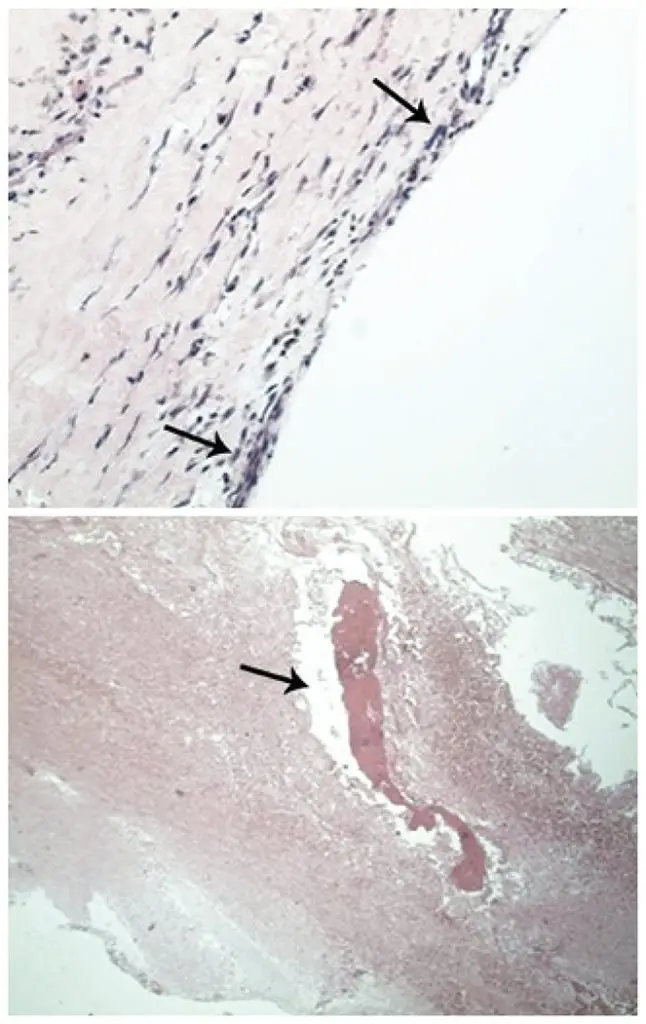

Lumbar synovial cysts are an uncommon cause of back pain and radiculopathy, usually manifesting with gradual onset of symptoms, secondary to involvement of the spinal canal. Rarely, intracyst hemorrhage occurs, and may acutely present as radicular – or even spinal cord – compression syndrome. Synovial cysts are generally associated with degenerative facets, although the pathogenesis has not been entirely established. We report a case of bleeding complication in a synovial cyst at L2-L3, adjacent to the right interfacet joint, causing […]